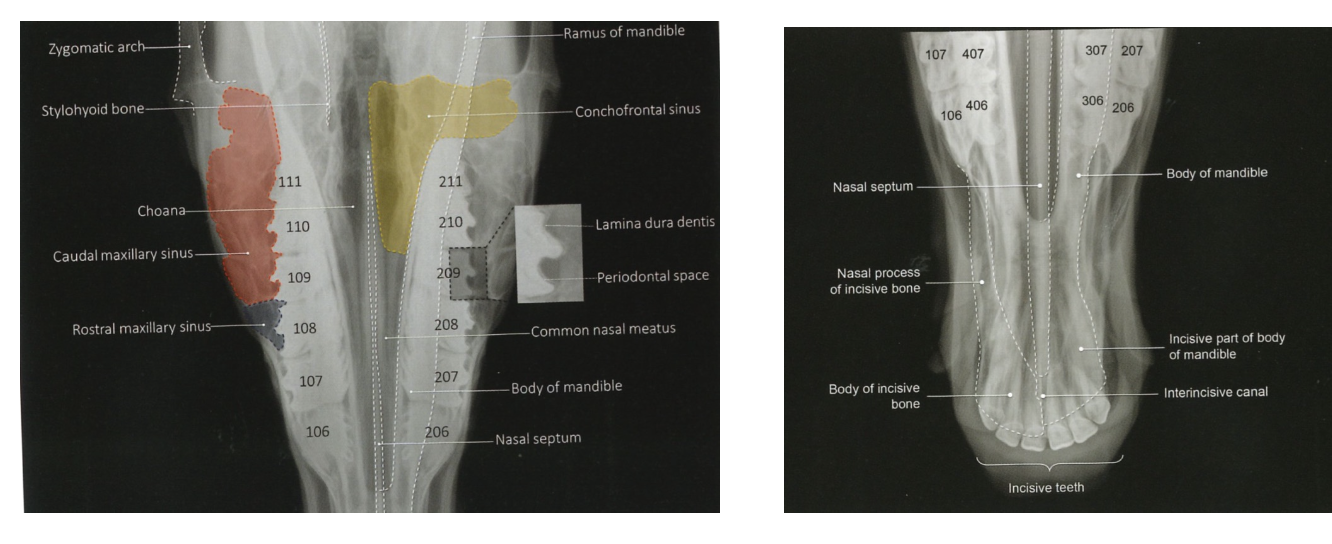

When is a dorsoventral view used?

Assessment of paranasal sinuses, nasal septum & teeth

Helps to determine if lesions unilateral/bilateral

Normal dorsoventral view anatomy

When is intra oral view indicated?

Assessment of incisor teeth & associate bone

Fractures of incisor teeth/associated bone, EORTH (EQ odonoclastic tooth resorption & hypercementosis)